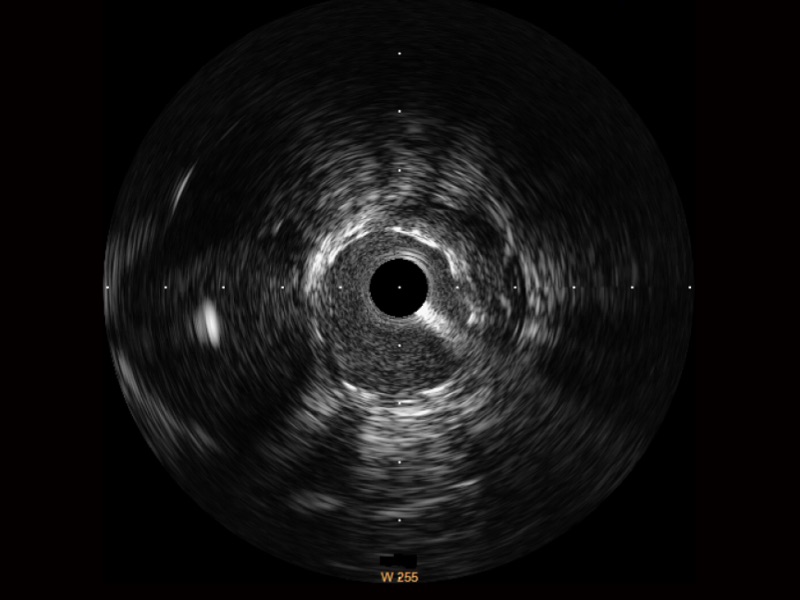

血管内超声(IVUS) 通过对病变程度、性质和累及范围的精确判断,可帮助选择治疗策略和方法,指导介入治疗过程,能够降低主要不良心血管事件,改善预后,在复杂病变介入治疗中用于指导支架置入的优势更为明显。血管内超声(IVUS)已成为精准心血管介入治疗的“金标准”。

db真人体育官网超宽频成像技术覆盖20-80MHz1或20-90MHz2频率范围, 提供优异的分辨力同时也保证充足的穿透深度

对比传统IVUS导管成像,db真人体育官网宽频IVUS图像的近场支架梁显影更细腻,远场中膜外血管仍清晰可辨,兼顾远中近,兼顾分辨力与穿透深度